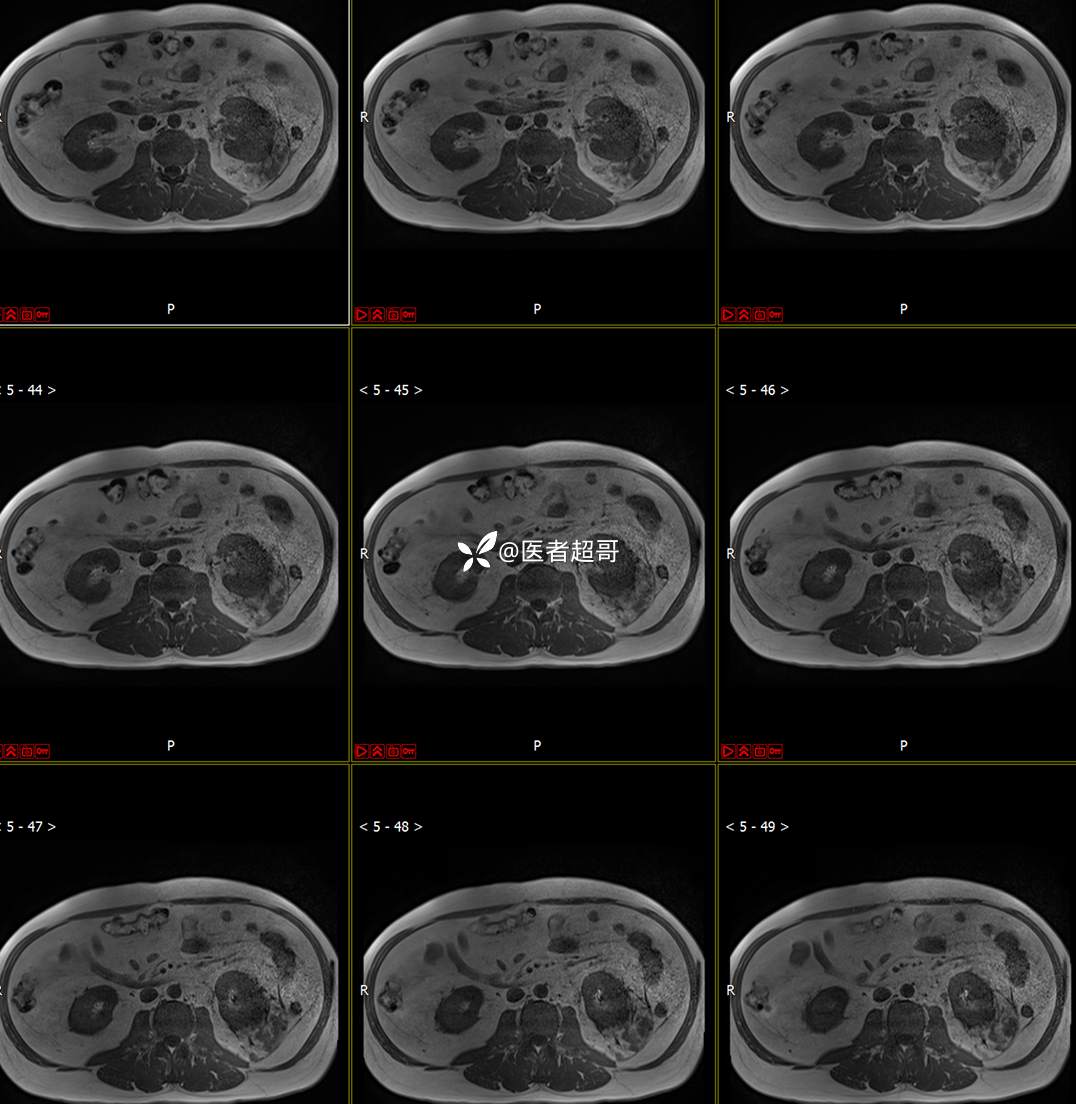

主 诉:查体发现左肾肿物9天。

现病史:患者9天前于附属医院行常规腹部CT检查时,发现左肾占位性病变并肾周脂间隙软组织增多,自述无明显腰腹部不适,无尿频、尿急、尿痛及肉眼血尿,未予特殊治疗,患者近期无头晕头迷,胸闷气急,腹胀腹泻及其他部位明显不适,遂至我院就诊,门诊以“肾肿物”收入院,患者自发病以来,精神可,睡眠饮食可,大便正常,体重无明显减轻。